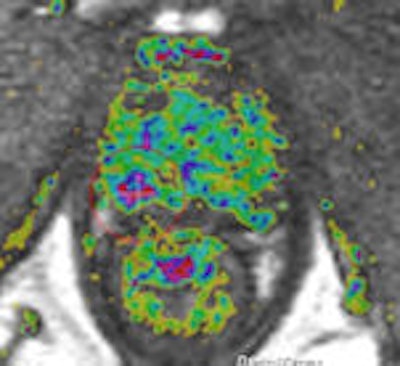

A 69-year-old male three years post electron-beam radiation therapy (EBRT, primary PC: Gleason 4+3 right PZ) with PSA increase to 2. MRI and TRUS-guided biopsy of this area confirmed Gleason 4+4 recurrence at right PZ (old tumor location). Left: Axial T2-weighted MR image shows low signal prostate due to previous EBRT. Therefore, tumor (arrow) is difficult to see. At arrow, there is some "bulging" (PI-RADS 5). Center: Axial DCE-MRI shows increased focal asymmetric contrast leakage at right PZ (circle, PI-RADS 5). Right: Axial ADC-map of DWI-MRI shows restriction (low signal, circle, PI-RADS 5). Final diagnosis: PI-RADS 5. TRUS biopsy of this area confirmed Gleason 4+4 recurrence."Prostate imaging at 3-tesla benefits from higher signal-to-noise ratio and enables high-quality imaging within a short time without the use of an ERC [endorectal coil]. Data on 3-tesla for prostate cancer MRI are still conflicting. Thus, further research on this topic is needed," the authors noted. "Limitations of 3-tesla MRI are shorter T2- and longer T1-relaxation times, problems with susceptibility artifacts, dielectric effect, specific absorption rate, and the homogeneity of the magnetic field. However, hardware, multichannel coil, and parallel imaging technique improvements are currently solving most of these problems."